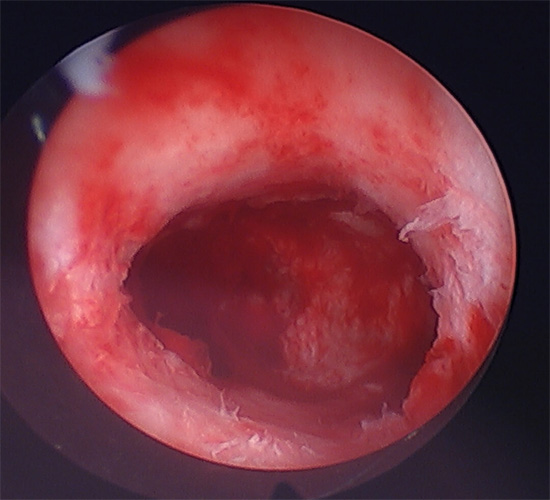

Hysteroscopy

Hysteroscopy is a minimally invasive procedure used to diagnose and treat uterine conditions, improving fertility and overall reproductive health.